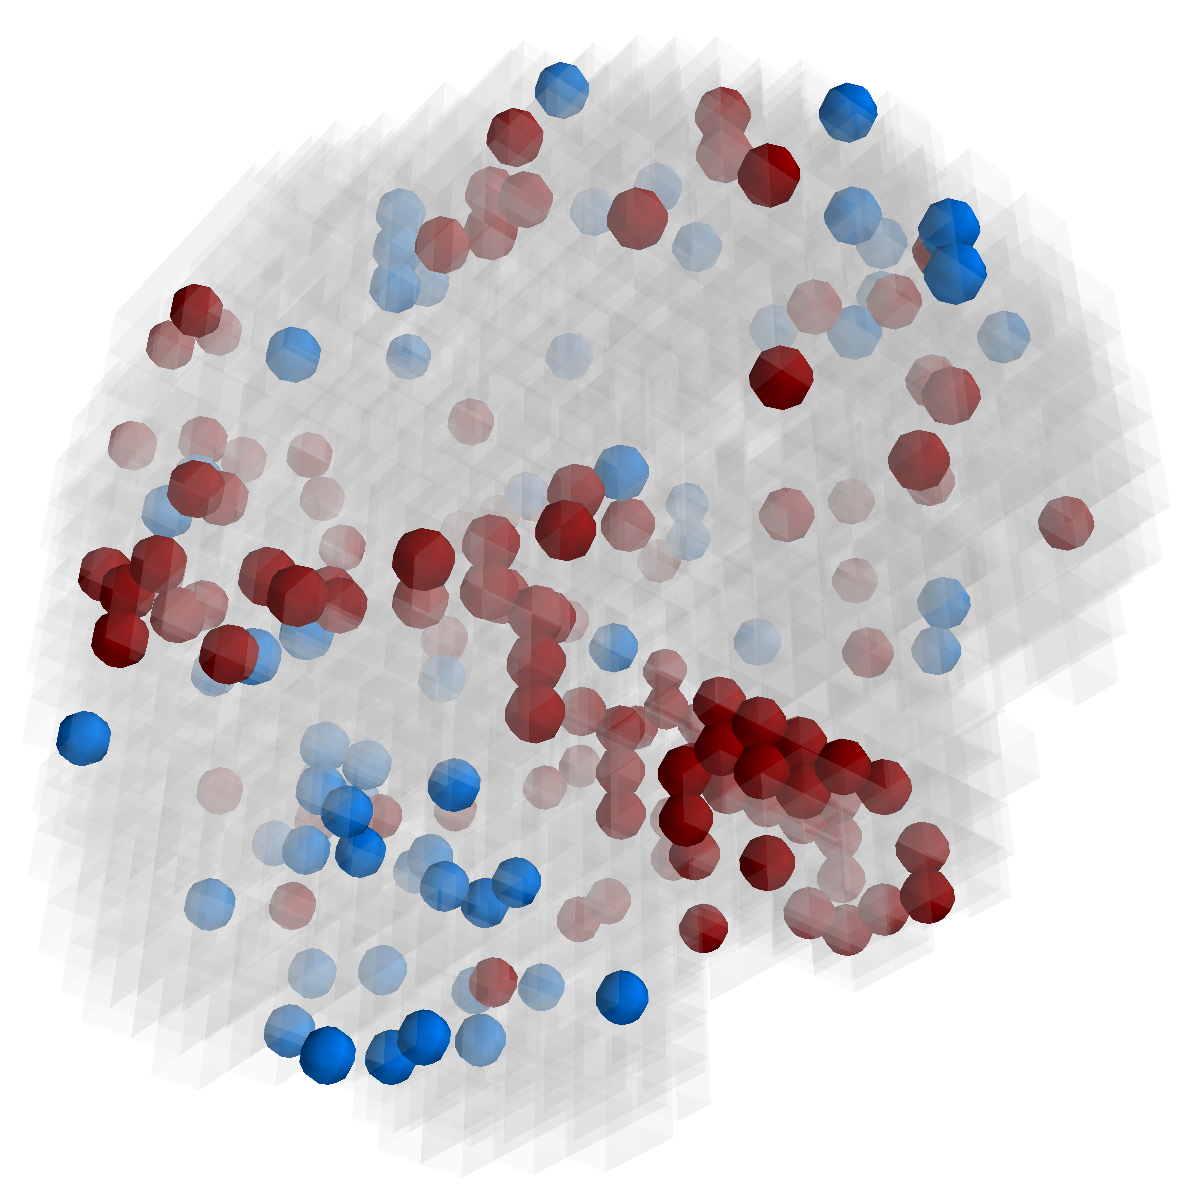

Figure 2: Feature selection by different models. The top row illustrates selected voxels in a 3D model (voxels with positive β𝛽\beta are in brown and negative ones are in blue), the mid and bottom rows illustrate the corresponding projections on brain slices.

Feature selection. For each task, the selected features are those whose β𝛽\beta are not zero . In Figure 2, the result of 30ADNC is used to illustrate the feature selection by different models (using the parameters at their best accuracy). As shown, the selected voxels by both GFL and n2superscript𝑛2n^{2}GFL cluster into several spatially connected regions, whereas those of lasso and T-test/MLDA scatter around. Also, as mentioned before, the LapL tends to select much more voxels than necessary due to the l2subscript𝑙2l_{2} regularization. Moreover, the selected voxels by GFL and n2superscript𝑛2n^{2}GFL are concentrated in Hippocampus, ParaHippocampal gyrus (which are believed to be the early damaged regions). On the other hand, the lasso and T-test/MLDA either select less lesion voxels or select probably noisy voxels not in the early damaged regions.